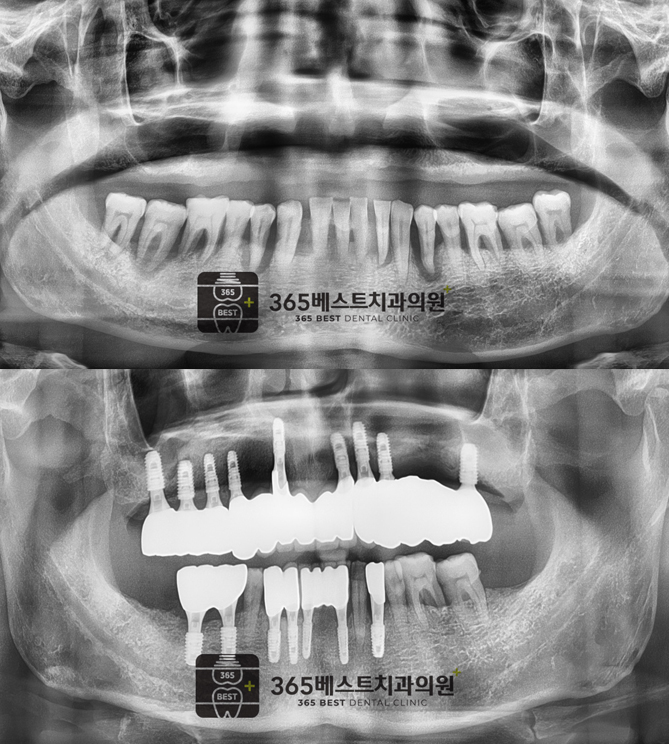

전후사진